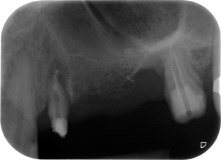

Mujer de 58 años de edad, que además es una apreciada colega y amiga, y se quejaba de dolor y de un aumento en la movilidad del pilar del puente de la pieza dental 24. También había inflamación periodontal, con bolsas de una profundidad de 7 mm en sentido mesiobucal y más de 12 mm en sentido distal, así como furcación de tercer grado. Asimismo, la radiografía reveló una lesión periodontal extensa alrededor de la región apical de la pieza dental 24 (figura 1) tratada previamente con endodoncia (alio loco).

Un mes después, en el día de la intervención, el dolor y la inflamación se habían reducido al mínimo en la pieza 24, pero seguía habiendo una movilidad de clase II de Miller. Después de la apertura de los colgajos y de la limpieza del tejido infectado periapical y perirradicular, la extensión del defecto óseo quedó evidente (figuras 2 y 3).

En la raíz bucal, faltaba todo el hueso vestibular y distal. Básicamente, la fijación se limitó a la raíz palatal, lo que corroboró el mal pronóstico preliminar. La pieza 27 también mostró una fijación horizontal reducida (figura 12) y una rarefacción apical mínima (figura 1), si bien sin síntomas clínicos.